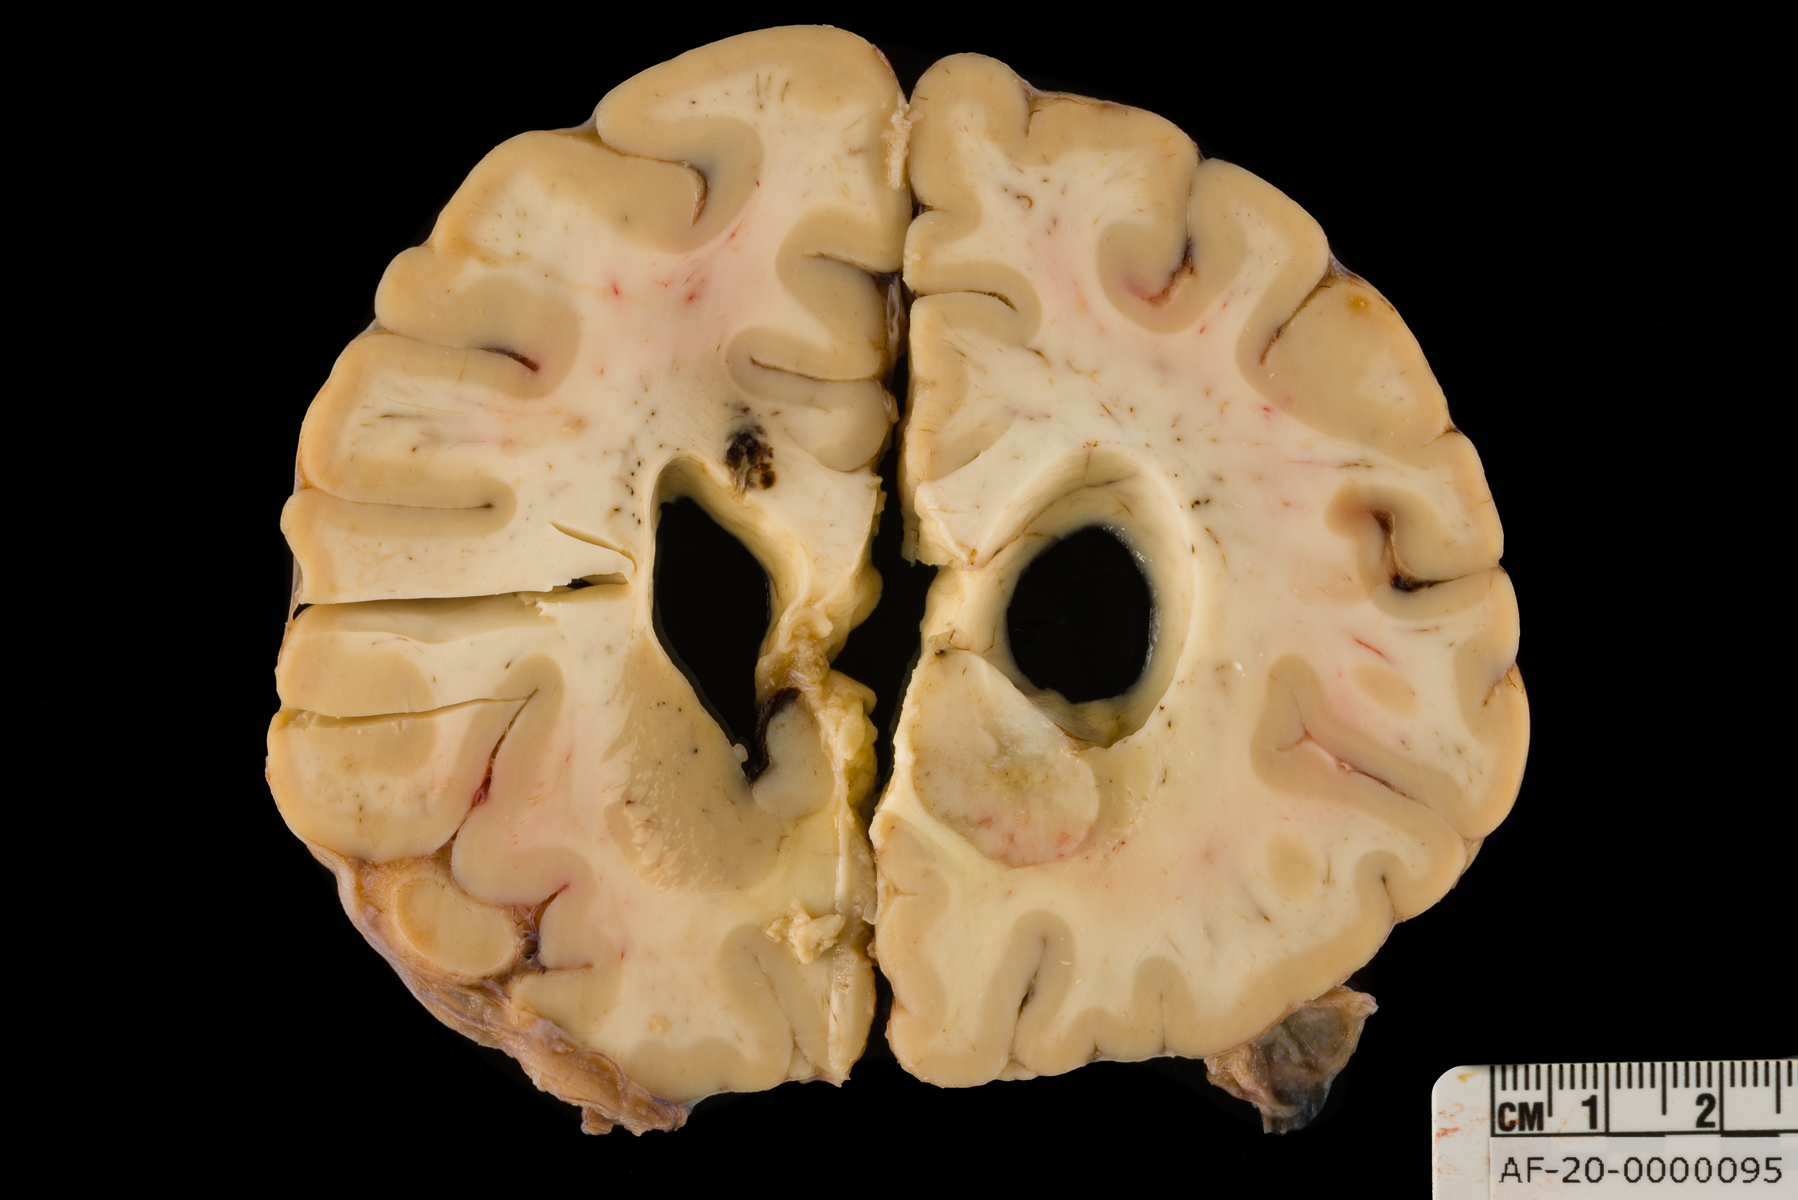

Case 5